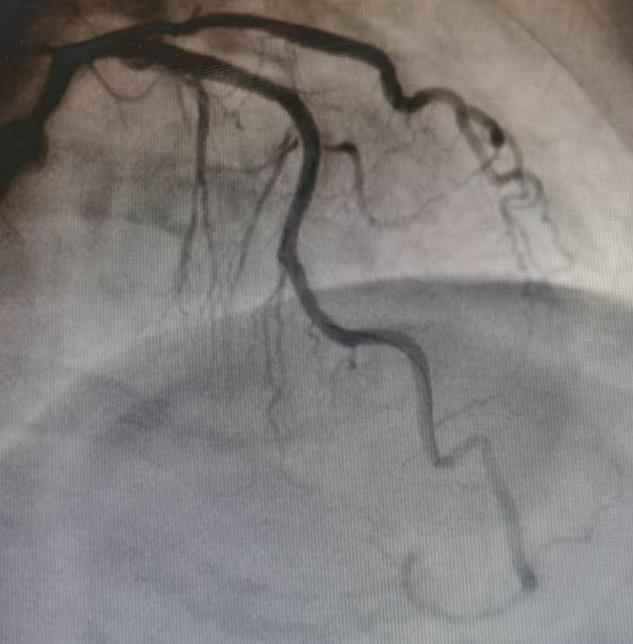

患者吕奶奶今年71岁,因反复严重胸痛入院。冠状动脉造影结果令医生们深吸一口气:心脏最重要的“生命主干道”——左前降支近段,被严重钙化斑块紧紧堵塞,狭窄程度超过95%,血管壁坚硬如石,在X光下呈现出典型的“脊背样”钙化影,IVUS显示360度环形钙化。

冠脉造影显示前降支严重狭窄伴钙化